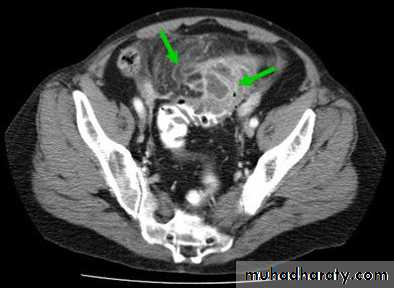

CT signs of acute diverticulitis include

• Localized bowel wall thickening• Soft tissue stranding or haziness in pericolonic fat.

• Gas in the bladder may indicate formation of a colovesical fistula.

• Abscess.